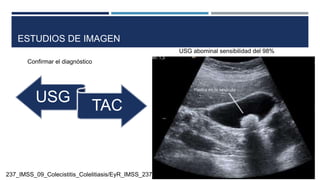

ESTUDIOS DE IMAGEN

USG

TAC

Confirmar el diagnóstico

USG abominal sensibilidad del 98%

ESTUDIOS DE IMAGEN USG TAC Confirmarel diagnóstico USG abominal sensibilidad del 98% 237_IMSS_09_Colecistitis_Colelitiasis/EyR_IMSS_237_09.pdf